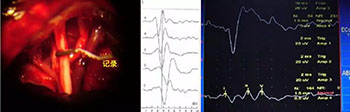

↓术中电生理监测举例↓

听神经动作电位